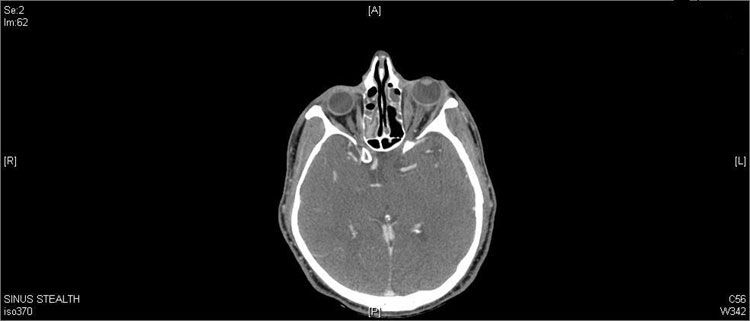

A 58-year-old man with a past medical history of chronic sinus disease and hypothyroidism presented with left periorbital pain and erythema that worsened despite outpatient treatment with topical antibiotics. An outpatient CT scan showed pansinusitis and orbital stranding (Figure 1). The diagnosis was orbital cellulitis and sinusitis.

Figure 1

Results of bloodwork, including blood cultures and thyroid studies, were unremarkable except for a peripheral eosinophilia of 11%. At this time, a CT showed complete pansinusitis and left orbital fat stranding.